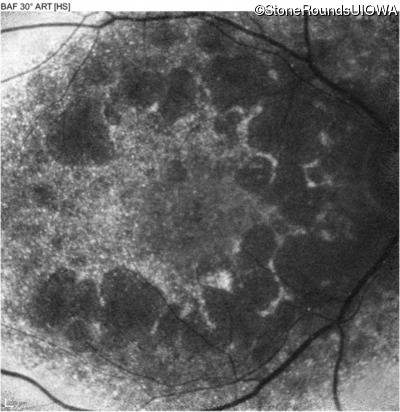

Blue Autofluorescence - Left - 10/400 sc

Exemplar